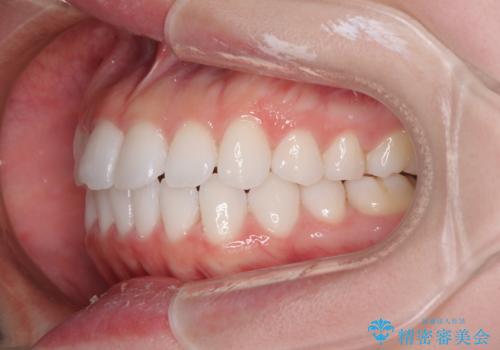

- 矯正装置

- 審美装置

- 海外留学を前に上下のデコボコと奥歯の咬み合わせを改善したいとのことで来院された患者様です。

期間が限られていたため、ワイヤー装置による矯正治療を行うこととしました。

治療開始から4ヶ月ほどで概ね歯列が整い、その後の3ヶ月で細かい部分を仕上げていきました。

短期間で綺麗に仕上がり、患者様には大変満足していただきました。